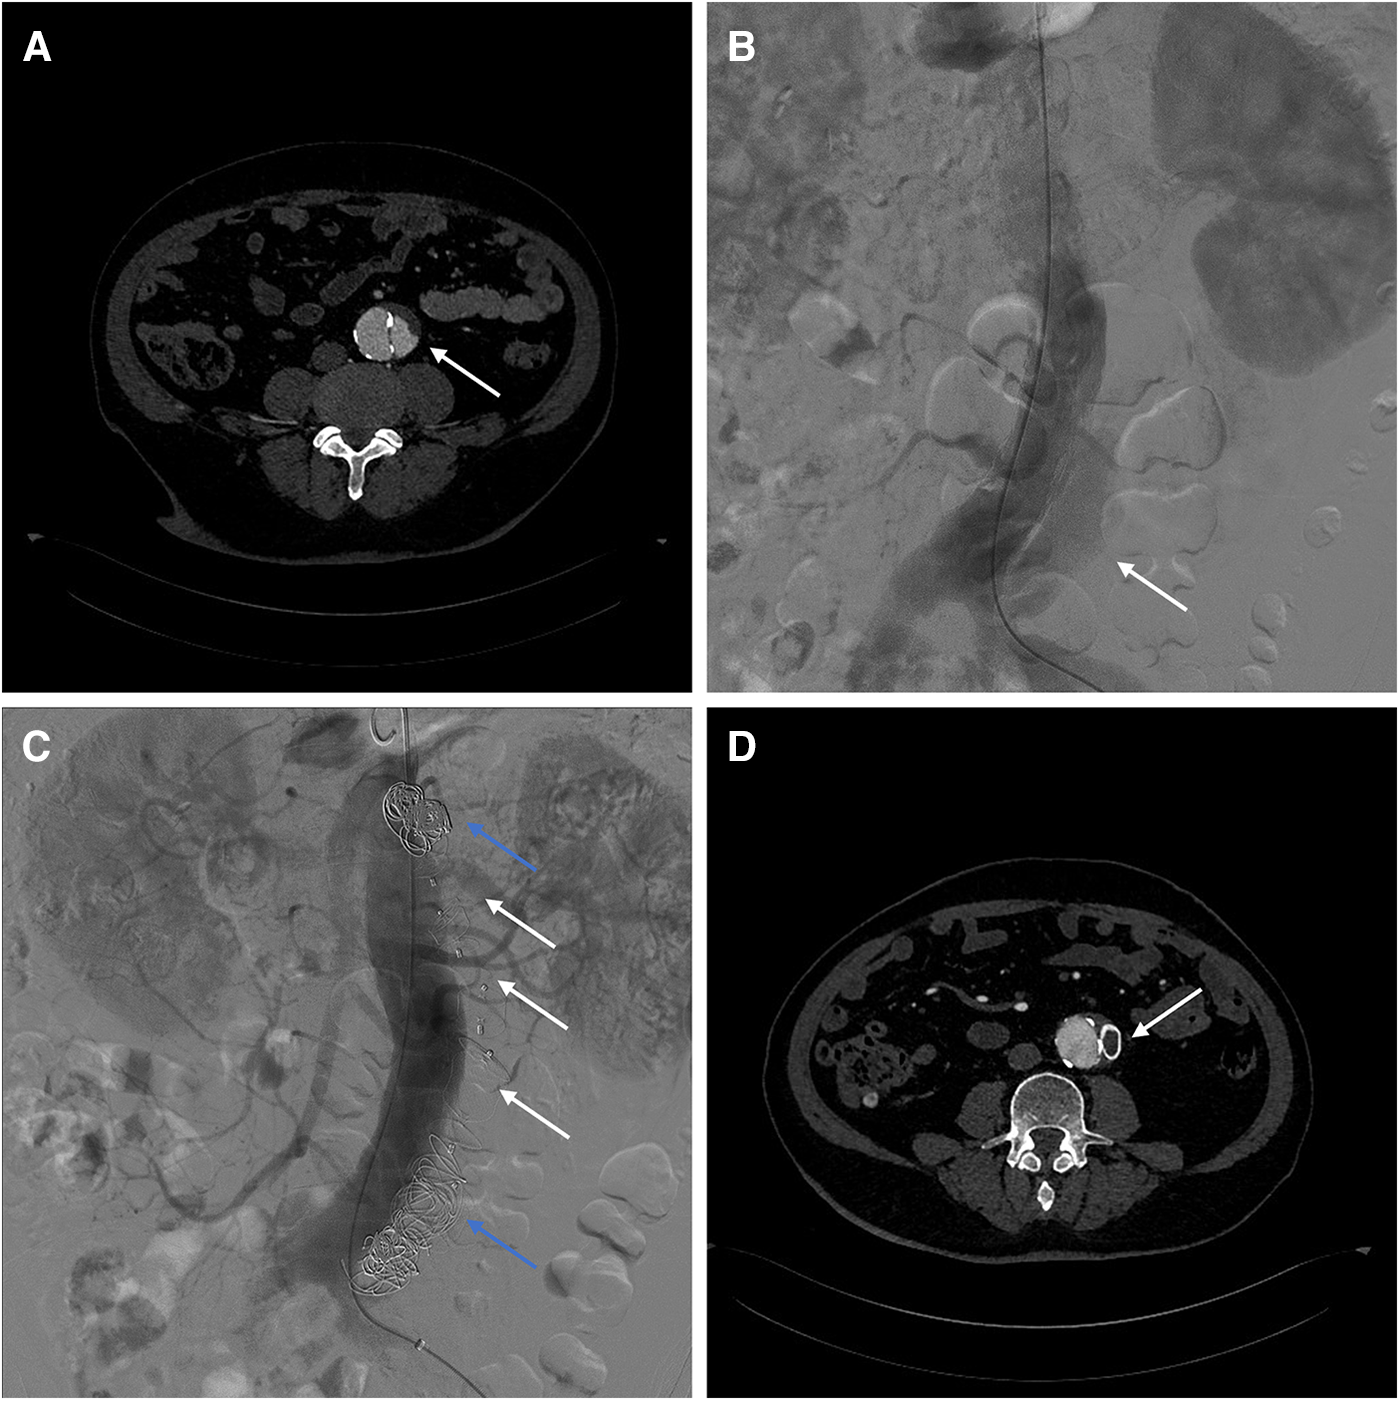

Case 2: A 62-year-old male underwent fenestrated or branched endovascular aortic repair (F/B-EVAR) for aortic arch and thoracic aorta 9 months ago for type B aortic dissection. Post-surgery CTA revealed a 57 mm Post-dissection abdominal aortic aneurysm extending to both iliac arteries. Multiple tears were located at the level of the celiac trunk and bilateral iliac arteries (Figure 3A).

Figure 3

(A) Preoperative CTA showed blood flow in false lumen of aorta. (B) Intraoperative angiography showed the false lumen opacification in abdominal aorta. (C) Angiography showed no opacification of the false lumen after AVPs (white arrow) and coils (blue arrow) placement. (D) 3-month post-surgery CTA shows AVP in abdominal aorta.

To avoid complex endovascular techniques, the goal is to reconstruct the aneurysm's neck as a healthy anchoring site before implementing standard EVAR in the second phase. Under local anesthesia, the false lumen is accessed through an intimal tear in the left iliac artery (Figure 3B). Due to limited space, several Interlock mechanically detachable coils (Boston Scientific, Natick, MA, USA) were inserted at the level of the celiac trunk artery. After that, AVP II with diameters of 14 mm, 18 mm, 20 mm, and 22 mm were released sequentially in the false lumen. Finally, multiple coils (COOK, Bloomington, IN, USA) were placed at the distal false lumen to aid with embolization. Angiography confirmed no false lumen opacification (Figure 3C). Postoperative CTA examination after 3 months showed complete thrombosis of the false lumen in the abdominal aorta. The diameter of the abdominal aorta decreased from 57 mm to 47 mm, while the diameter of the true lumen increased from 22 mm to 37 mm (Figure 3D). Therefore, a second-stage EVAR surgery is not necessary.